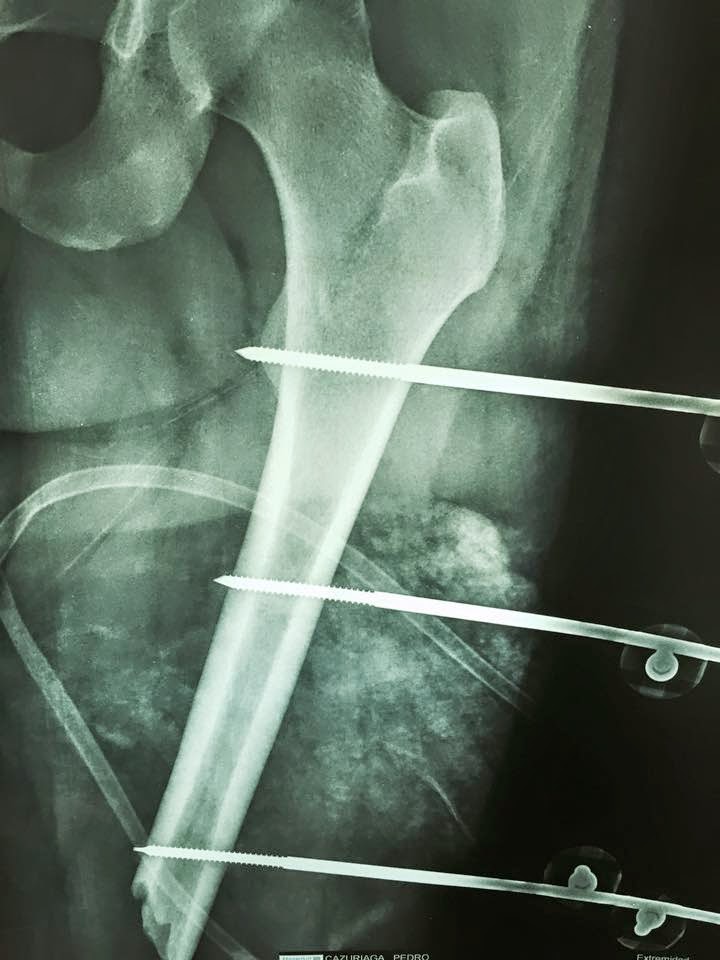

Fractura expuesta grado III B de femur izq. Fx. Cerrada de tibia izquierda. Rodilla flotante. No tiene y no se como pero no tiene lesión vascular ni tampoco neurológica ya estabilizado con Fij. ext y VAC. No tiene otras lesiones.

- Christian Fuentes Bazan Asi es la perdida calculada es de 11 cm. Analizando la metáfisis distal tiene trazo intercondileo y con varios fragmentos, por lo que colocar fijador o los schanz distales tienen alto riesgo de aflojamiento.

- David Hernández Mújica Transporte oseo segmentario con fijador LRS hay que poner cabezal ennlos condilos prrlq tambien anclajes a tibia una vez colocado un centromedular a la tibia, tenemos un caso de 23 cm en SROA en fémur